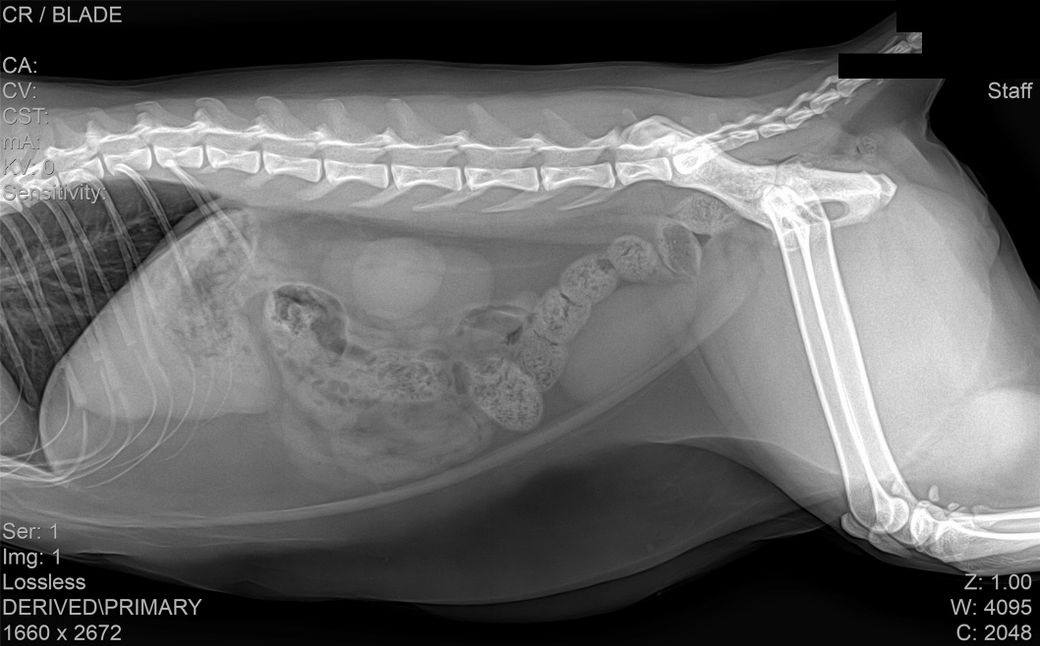

건강검진 때 받은 사진입니다

건강검진 받은 병원에서는 따로 소견을 주지 않으셨으나 지인이 이 사진을 보고

자신의 첫째 고양이가 진단 받았었던 HCM과 엑스레이 사진이 유사하다는 말을 들어서요

HCM의 경우 방사선 상으로는 완전히 진단하는 것이 어렵습니다.

진단을 하려면 영상전문 수의사로부터 심장초음파 소견을 듣는 것이 정확합니다.

HCM이 심할 경우 심장 모양이 valentine shape으로 보이기도 합니다. 아무래도 수의사 선생님이 이런 양상으로 HCM 가능성을 말씀하신 듯하니 심장초음파 진료가 가능한 병원 가셔서 검사 해보시기 바랍니다.

HCM의 진단의 golden standard 는 심장초음파 검사입니다. 하지만 첨부된 자료에는 심장 초음파 검사 결과가 없고

흉부 방사선 검사 또한 외측상이 결여되어 있어 자료로 판단할 수 없습니다.

주치의에게 요청하여 심장 초음파 검사를 진행해 보시기 바랍니다.